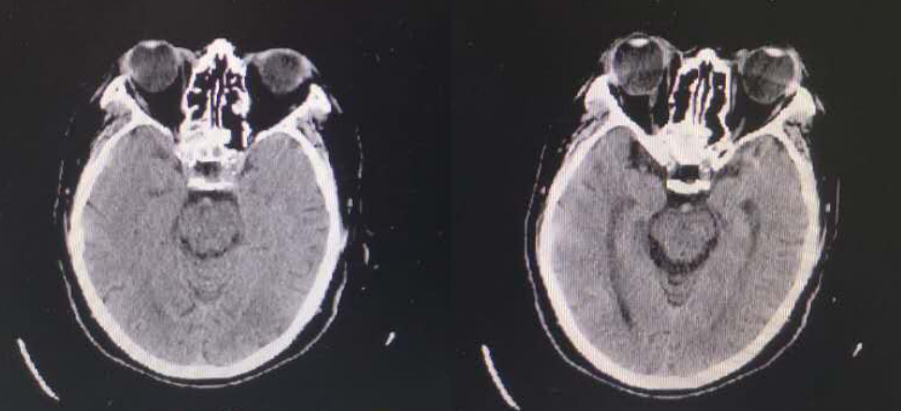

术前头颅CT示

1. 脑内散在腔隙性脑梗死;2. 左侧大脑中动脉近段管腔密度略增高。

术后复查CT未见出血

该患者术前头部CT未见明显出血且发变时间均在手术范围之内,符合急诊取栓手术指征。术中造影提示患者左侧颈内动脉起始部闭塞合并狭窄、左侧大脑中动脉闭塞,急性颈内动脉起始部闭塞合并狭窄是急性缺血性脑血管病中较为严重的一种类型,脑梗死范围常常累及整个大脑中动脉及大脑前动脉供血区域,静脉溶栓血管再通率低,仅为10%左右,急性颈内动脉闭塞预后极差,虽然目前多项研究表明支架取栓或直接抽吸取栓能够改善其预后,但仍面临挑战。在颈内动脉取栓的过程中,由于其特殊的分叉结构,血栓可能向大脑前动脉或者大脑中动脉发生移位或逃逸,也有可能向对侧逃逸,这造成了此处取栓的困难。本例患者在行颈内动脉支架取栓+抽吸后,复查造影提示颈内动脉起始部重度狭窄、左侧大脑中动脉闭塞,考虑串联性病变,再次行支架取栓+抽吸术开通大脑中动脉保证大脑血供,在左侧颈内动脉起始部放置一枚支架,复查造影支架贴壁良好颅内段血供良好。患者术后复查头部CT提示出血,给予对症支持治疗后好转,后期在康复科行康复治疗后出院。